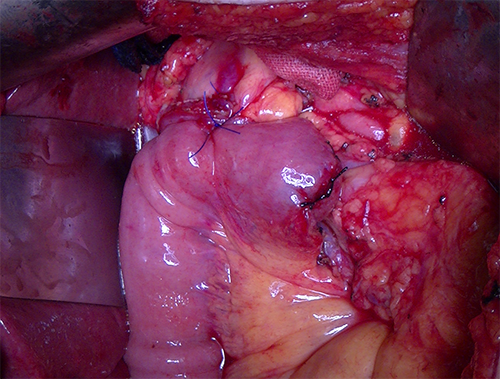

胰头癌-胰十二指肠切除